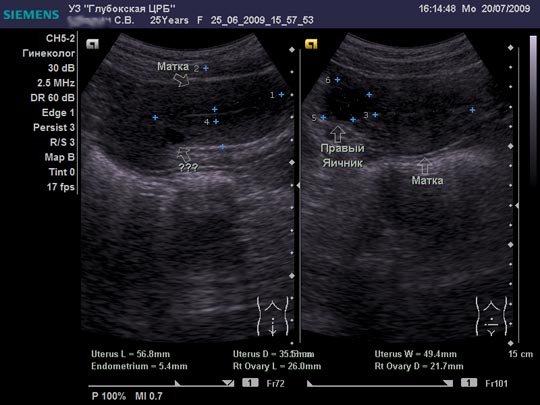

Женщина 25 лет предъявляет жалобы на периодически возникающую болезненность в нижних отделах живота, боли появились около 6-8 мес. Менструальная функция не нарушена. В анамнезе кесарево сечение, ребёнку 2,5 года.

Я тоже думал про наботовы желёзки, но меня смутил тот момент, что не явилось ли это образование следствием оперированной матки, лигатуры... ну чего-то там с ними... или что-то в этом духе????

Согласен, Наботова или эндо-цервикальная киста шейки. Ничего специфического.

Naboti пишем, эндометриоз в уме

запросто. об эндометриозе надо думать, когда ov.nabotae несколько. и к тому же присутствуют гиперэхогенные линейные включенияDoc писал(а):Спасибо.